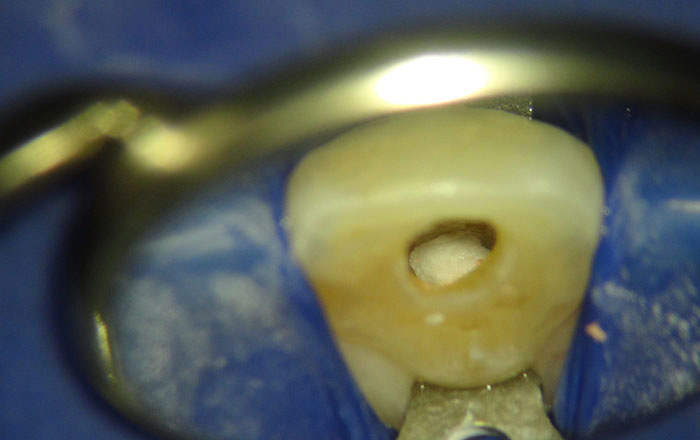

ウォーキングブリーチは、神経を取る治療の後、黒く変色した歯の歯髄腔に、歯を白くする高濃度の漂白剤を入れ、歯を内側から徐々に白くするホワイトニング方法です。

歯の内部には「歯髄腔」と呼ばれる神経が通っている部分があり、そこには神経と血管があります。

1)根管治療がきちんと行われたのを確認する

2)歯髄腔に薬剤を止めるための封をする

3)歯髄腔に薬剤を入れる

薬剤:30〜35%の過酸化水素水と過ホウ酸ナトリウムの混合されたペースト

4)封をする

5)歯科用のレジン(CR)で蓋をする